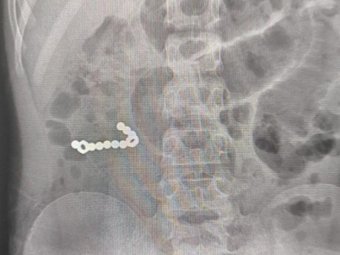

Пациента экстренно доставили в в Коряжемскую ЦГБ, где ему был сделан рентген. На снимке обнаружили множественные инородные тела в ЖКТ. Заведующий хирургическим отделением Дмитрий Кувакин провел вмешательство на органах брюшной полости и извлёк магниты из кишечника.